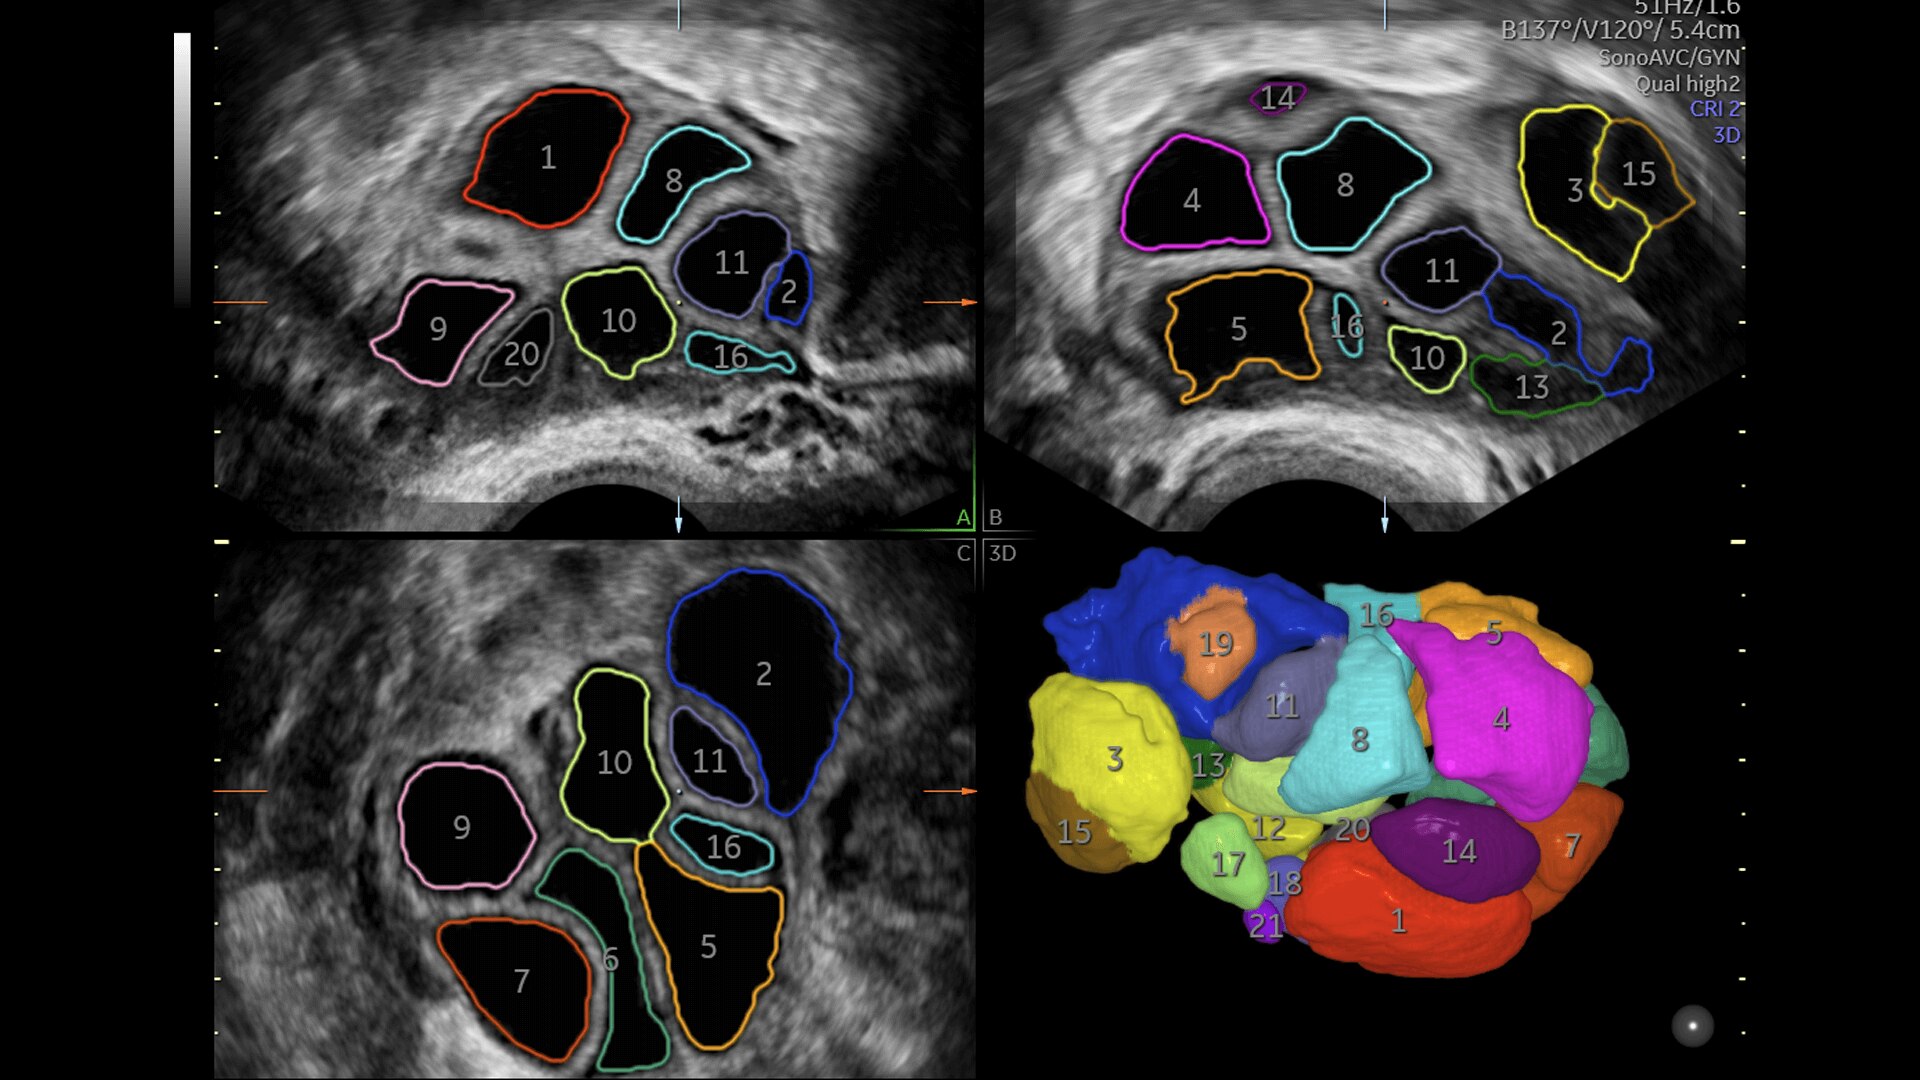

Pelvic Health

Offer patient answers faster with Ai-based automation tools